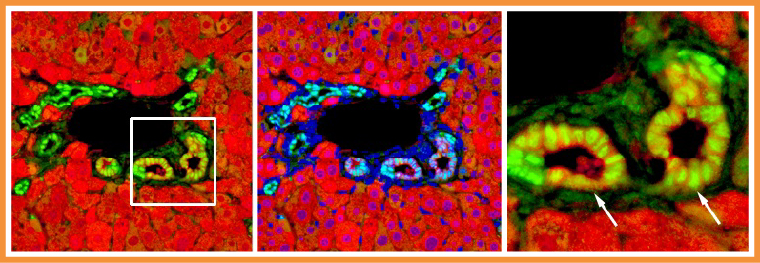

▲由肝細胞轉變而來的膽管上皮細胞。(圖/陽明交大生命科學系暨基因體科學研究所提供)

膽管的修復是肝臟多種自癒力表現之一。當膽管受損時,原本負責代謝功能的肝細胞竟能搖身一變為膽道上皮細胞,並且衝向前線修補受損的膽管。然而,這項轉變背後的分子機制長期未明。